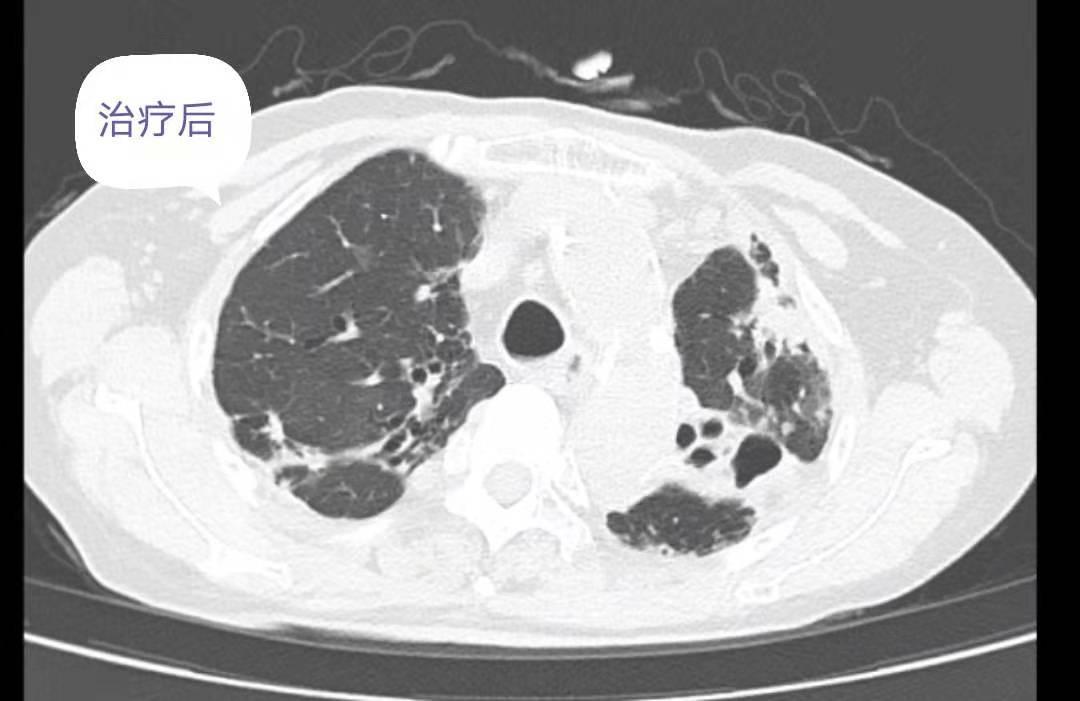

2019.08.16--2019.09.01 阿莫西林钠克拉维酸钾 1.2g q8h ivgtt,克拉霉素 0.5g qd po,左氧氟沙星0.5g qd po。治疗近2月后咳嗽、咳痰、气促等症状明显改善。查体:脉搏74次/分,呼吸18次/分,血压131/70mmHg。双肺呼吸音清,未闻及干湿啰音,心律74次/分,律齐。腹软,无压痛,无反跳痛及肌紧张,肠鸣音4次/分。

复查胸部CT:对比前片提示双肺感染灶减前吸收,肺气肿、支气管扩张,肺底少许纤维性病灶。患者病情改善后办理出院,随访期间未诉特殊不是。